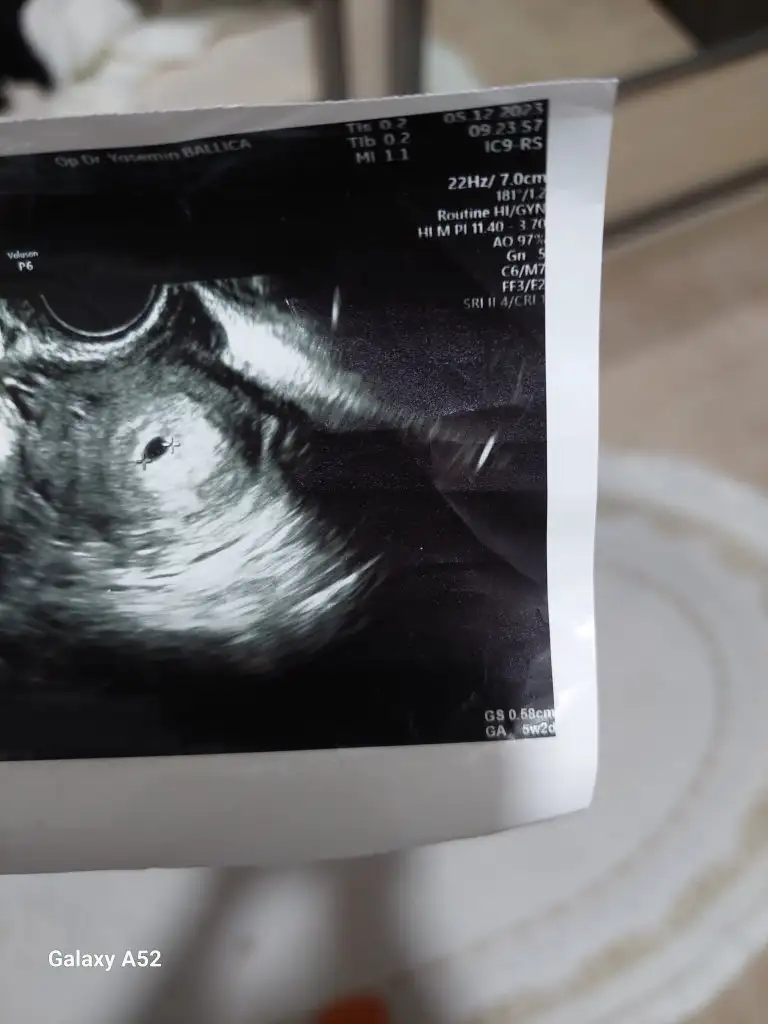

Kese boyutunu doktorunuz mu söylüyor yoksa ultrasyon görüntüsünde yazıyor mu kızlar4+6 yım canım kese boyutu 4.3 tü sanırım emin değilim![]()

ultrasonda yaziyor canim, benimki de 5.8 mmKese

Neresinde yazıyor kağıdınultrasonda yaziyor canim, benimki de 5.8 mm

Tam olarak nerde yazıyor yada ne olarak geçiyorultrasonda yaziyor canim, benimki de 5.8 mm

foto atayim bi dakikaNeresinde yazıyor kağıdın

sag alt kosede yaziyor benimkinde hem haftasi hem boyutu

Burası oluyor sanırım 6 haftalık boyut hangisi oluyor ?